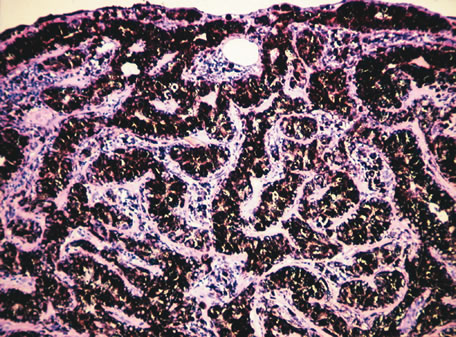

Retinochoroiditis

Necrotizing retinitis with secondary choroiditis is seen in protozoal infections such as toxoplasmosis or in herpetic infections. Infection with Toxoplasma gondii leads to retinitis and secondary choroiditis (Fig. 25), usually granulomatous.127 Congenital infection can be acquired in utero by transplacental transmission of the parasite from the infected mother to the fetus.128 Acquired disease occurs after ingestion of oocysts or tissue cysts.129–132 The congenital form of infection leads to atypical macular colobomas. Reactivation of the infection is caused by release of organisms that have remained dormant in the margins of old congenital retinal scars.133 The slowly proliferating form of the organism, termed the bradyzoite, can be seen in cysts. The rapidly multiplying form, termed the tachyzoite, may be difficult to identify in an infected retina or in immunocompetent individuals, but they are frequently seen in the retinitis of immunocompromised hosts.134 Active infection usually causes focal retinal opacification and an intense vitritis. These findings may give the appearance of a “headlight in a fog” in an immunocompetent person. In contrast, this clinical presentation is rare in patients with AIDS, in whom diffuse retinitis is observed with non-granulomatous choroiditis.134

Fig. 25. Toxoplasma retinochoroiditis. Necrotic retina shows cysts of toxoplasma gondii, and the choroid reveals granulomatous inflammation. (Hemotoxylin-eosin ×65.) Inset (Gomori methenamine silver ×160) shows cysts of the organisms.